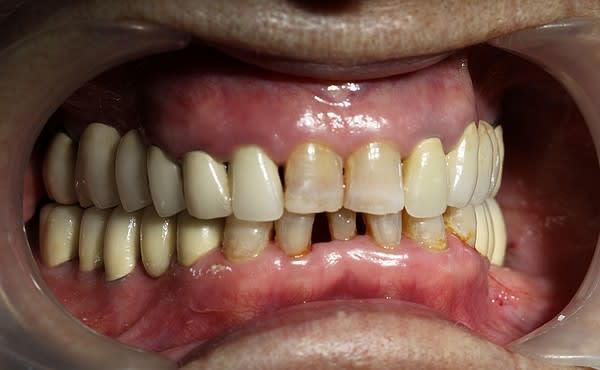

Cette même patiente, pimpante pour ses 90 ans et pleine de gaieté, viens me voir pour son nouvel appareil du bas qu'elle ne supporte pas. Avec surprise, je découvre dessous des chicots abandonnés par son ancien dentiste avec des inflammations gingivales. Radios prises, je lui propose de tenter de les récupérer pour lui réaliser des bridges en remplacement de son appareil, à l'inverse de ce qui se fait habituellement.

La racine résiduelle de la 37 était logée au fond d'un entonnoir gingival au ras de l'os et la 46 était trop délabrée pour la conserver entière. Après quelques séances de gingivoplasties et de tailles, le pari était gagné et les bridges ont pu être scellés, la patiente était radieuse!